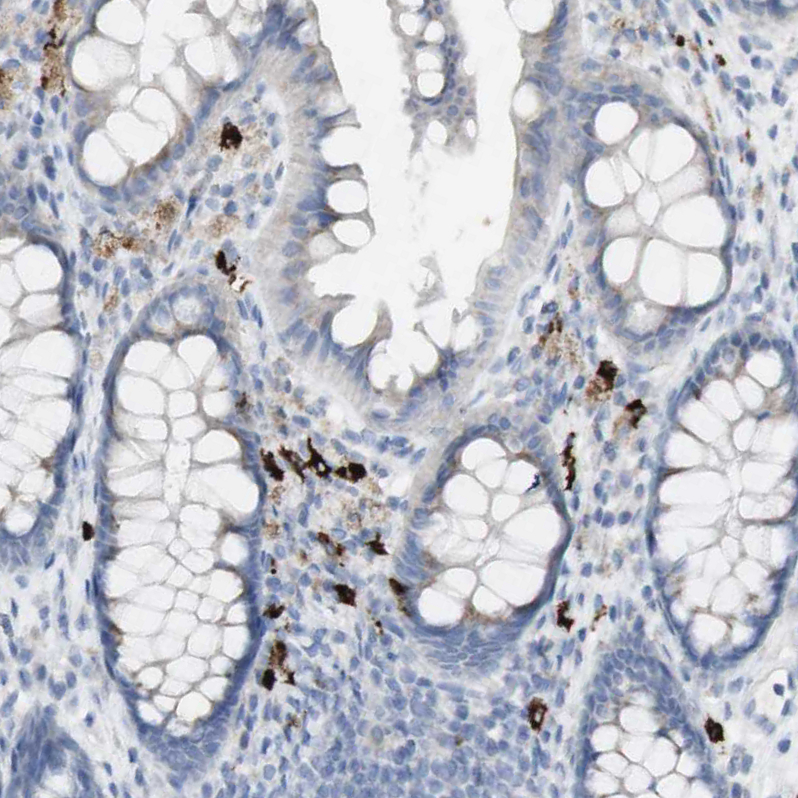

Immunohistochemistry analysis in human skin and pancreas tissues using HPA011216 antibody. Corresponding CD207 RNA-seq data are presented for the same tissues.